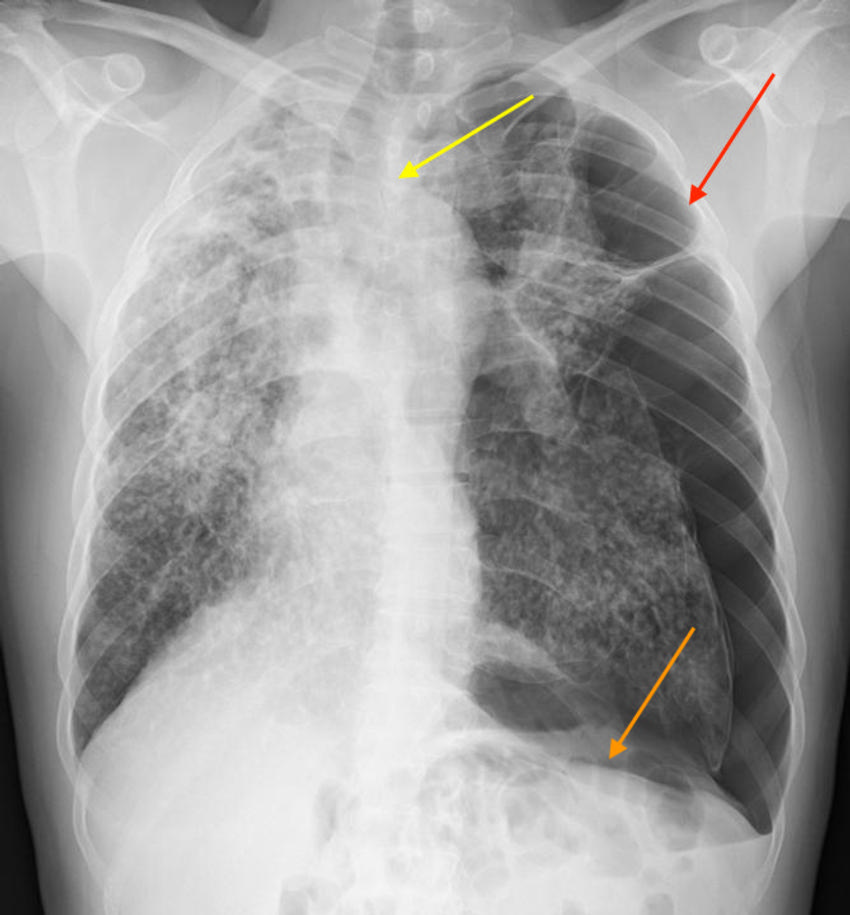

Figure 4. Follow-up chest x-ray. The patient was diagnosed with silicosis based on clinical history, imaging features, and bronchoscopy with biopsy, which demonstrated silica crystals with fibrotic nodules. There is persistent small left-sided pneumothorax/lung collapse (red arrow), asymmetric right upper lung thickening (yellow arrow), and findings consistent with progressive massive fibrosis (orange circle), indicating complicated and advanced silicosis. The patient is still working in the countertop-cutting industry due to lack of other job opportunities.